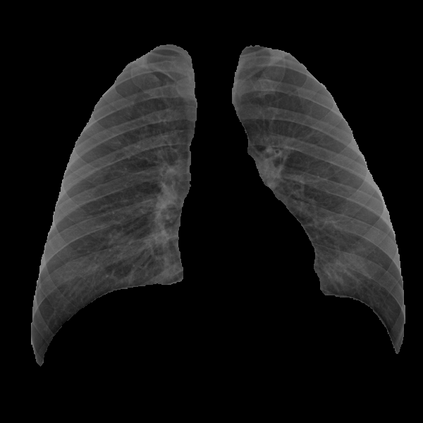

Deep learning technologies have already demonstrated a high potential to build diagnosis support systems from medical imaging data, such as Chest X-Ray images. However, the shortage of labeled data in the medical field represents one key obstacle to narrow down the performance gap with respect to applications in other image domains. In this work, we investigate the benefits of a curricular Self-Supervised Learning (SSL) pretraining scheme with respect to fully-supervised training regimes for pneumonia recognition on Chest X-Ray images of Covid-19 patients. We show that curricular SSL pretraining, which leverages unlabeled data, outperforms models trained from scratch, or pretrained on ImageNet, indicating the potential of performance gains by SSL pretraining on massive unlabeled datasets. Finally, we demonstrate that top-performing SSLpretrained models show a higher degree of attention in the lung regions, embodying models that may be more robust to possible external confounding factors in the training datasets, identified by previous works.